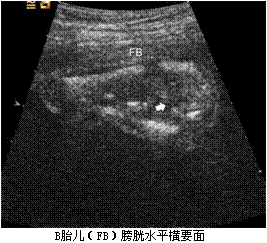

孕妇,30岁,孕2产0孕22周。超声(孕12周):宫内妊娠,单绒毛膜囊双羊膜囊双活胎,A胎儿NT0.32cm,B胎儿NT0.12cm。孕22周复查超声如下图。

孕妇,30岁,孕2产0孕22周。超声(孕12周):宫内妊娠,单绒毛膜囊双羊膜囊双活胎,A胎儿NT0.32cm,B胎儿NT0.12cm。孕22周复查超声如下图。<br /><img s